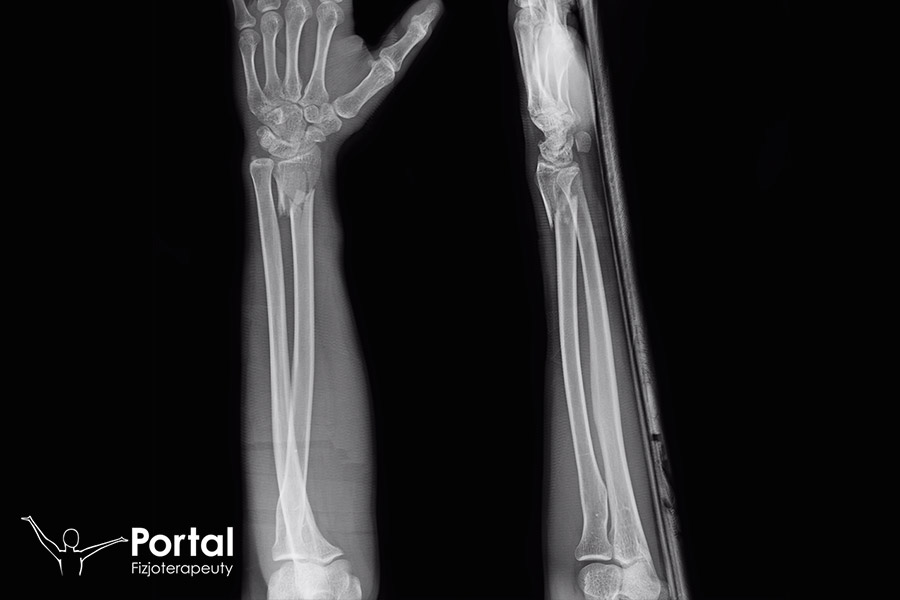

Złamanie Galeazziego

Złamanie Galeazziego dotyczy złamania trzonu kości promieniowej w jej 1/3 dalszej części, z jednoczesnym zwichnięciem stawu promieniowo-łokciowego. Wymaga natychmiastowej repozycji